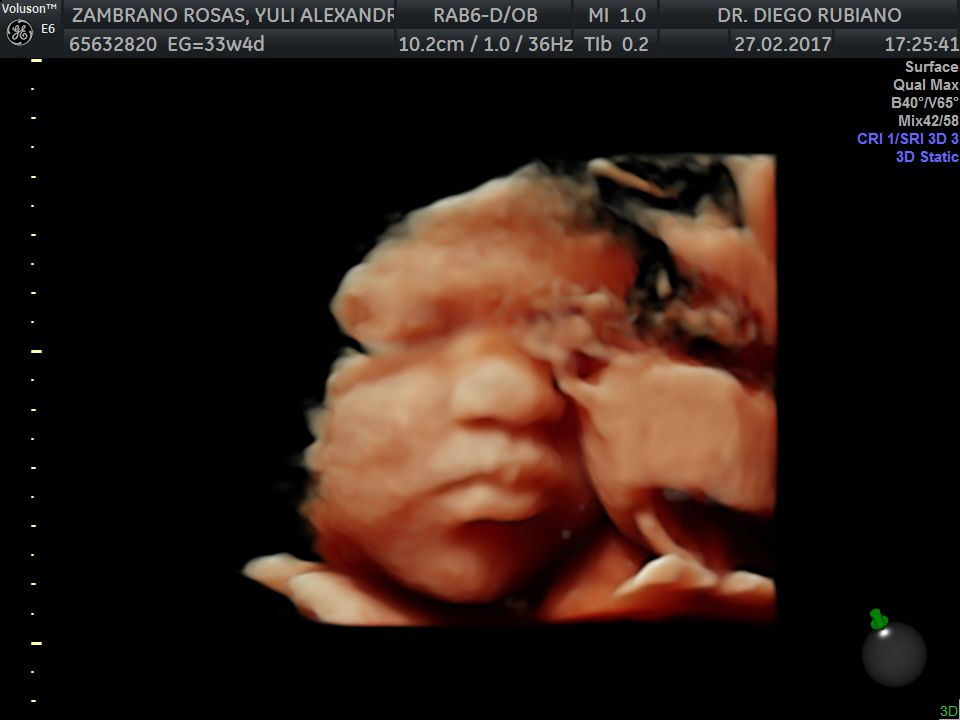

Fotos y videos

En nuestro consultorio médico, ofrecemos ecografías ginecológicas y obstétricas. Las ecografías ginecológicas son vitales para el control de la salud en mujeres no embarazadas, ayudando a detectar problemas temprano. Para futuras mamás, realizamos ecografías en todas las etapas del embarazo, utilizando equipos de alta tecnología para garantizar un seguimiento preciso del desarrollo del bebé. Ya sea que estés embarazada o no, nuestro servicio de ecografía está diseñado para cuidar de tu salud y bienestar.

• Consultorio privado Ecografía 3D  •